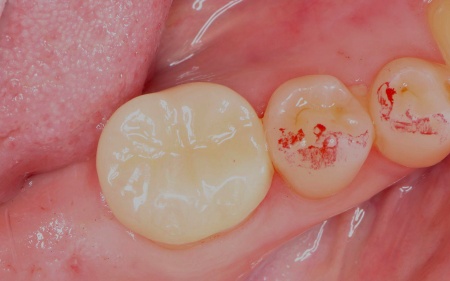

まず根管を丁寧に洗浄・消毒し、MTAセメントを用いて根の先端まで隙間なく密封しました。

その後、被せ物を装着するために歯の形を整え、型取りを行っています。

後日、完成したジルコニアセラミックが歯にピッタリと合っているか、噛み合わせに問題がないかを十分に確認した上で装着し、治療を終了しました。